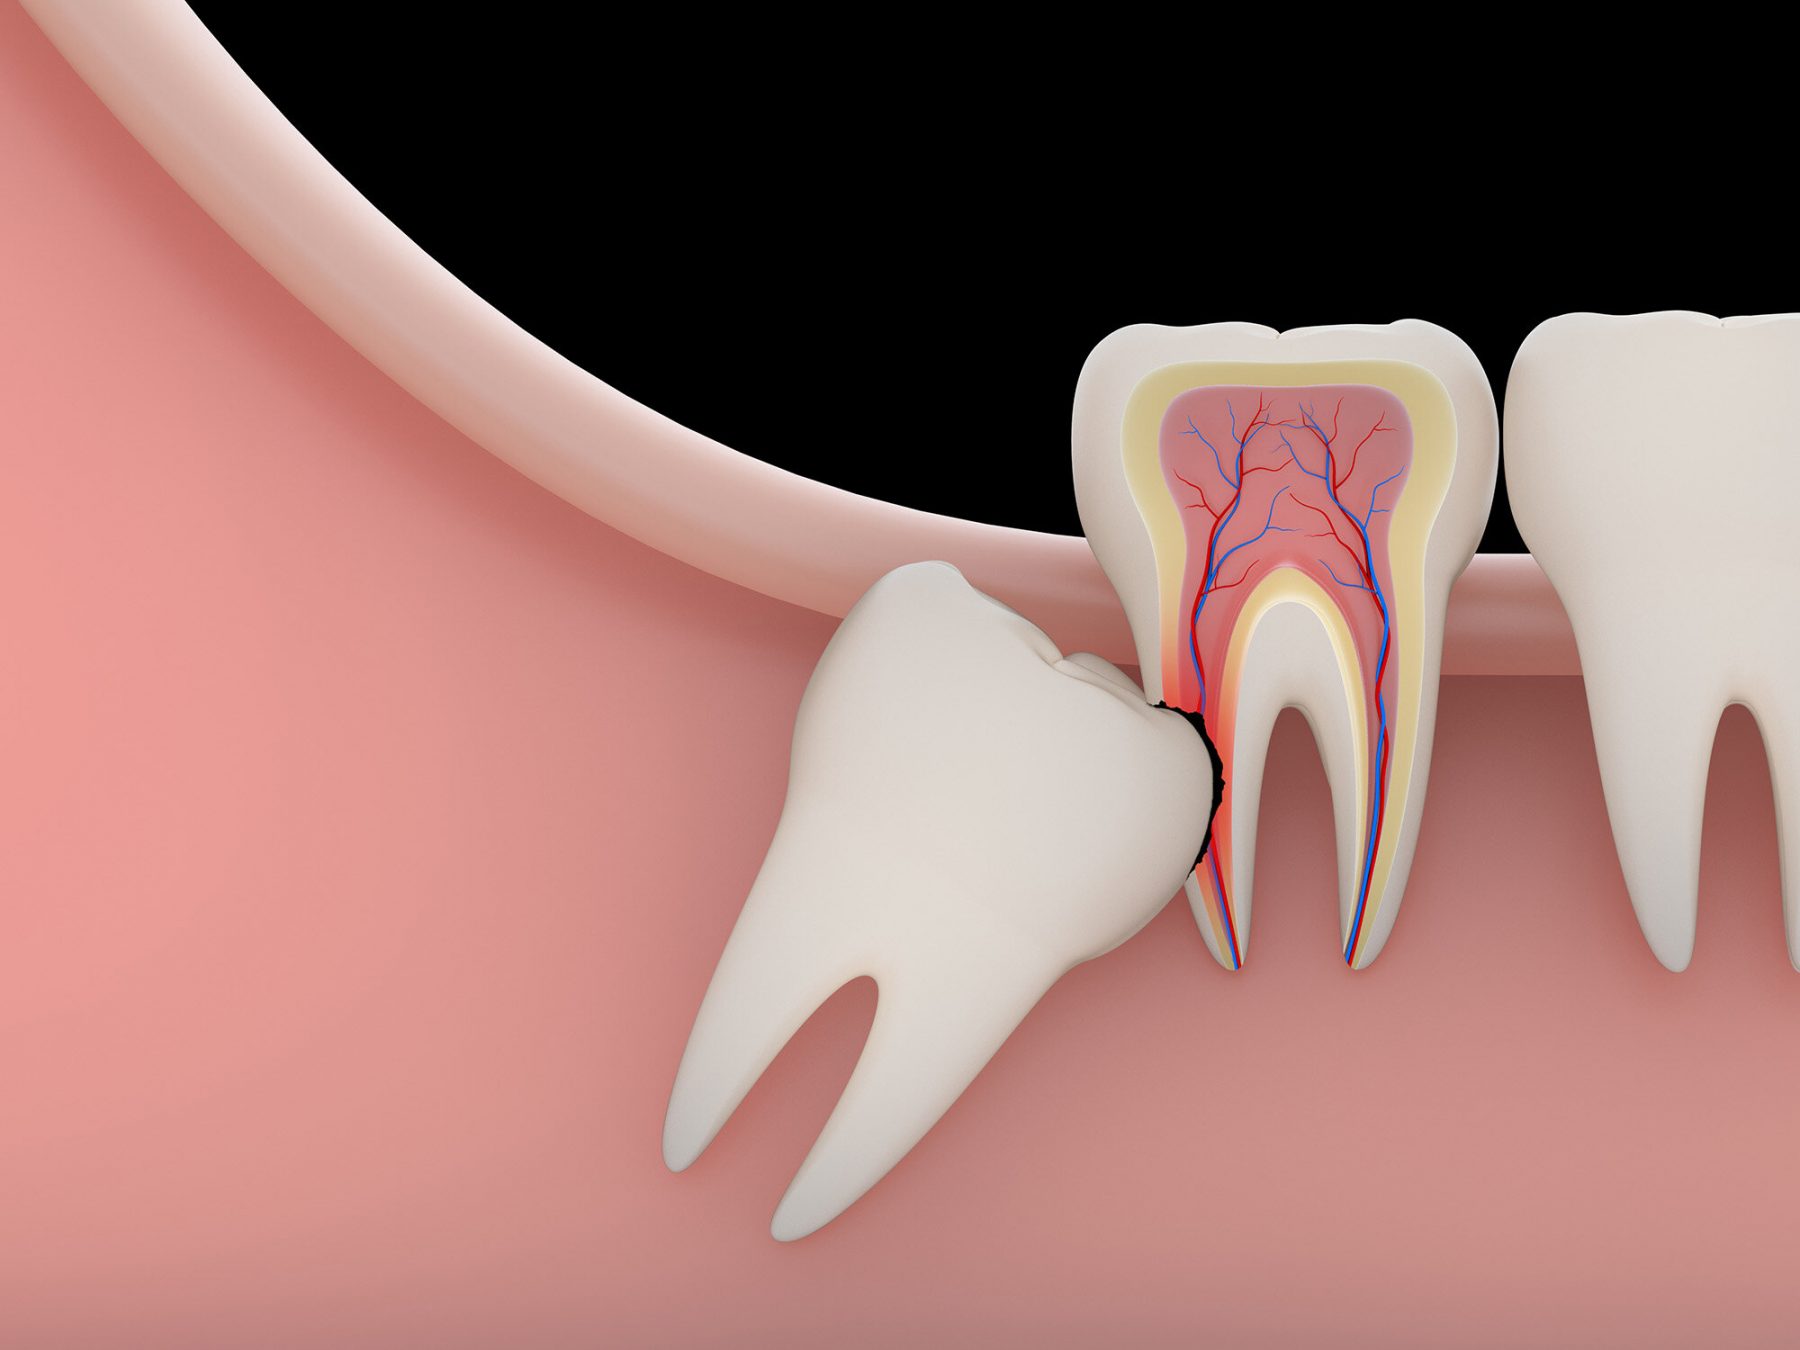

매복 사랑니 발치

매복 사랑니가 위험한 이유

비정상 각도·방향 → 옆 어금니 손상·충치

잇몸 염증·심한 통증 → 부기·발열·개구 장애

신경관 근접 → 방치 시 감각 이상 위험

2. 통증 완화를 위한 체계적인 솔루션

충분하고 세심한 국소 마취: 발치 부위를 정밀하게 마취하여 시술 중 통증을 거의 느끼지 않도록 합니다.

최소 침습 발치 기법: 불필요한 절개나 삭제를 최소화하여 시술 후 통증과 부기를 줄입니다.

개인별 맞춤 통증 관리: 시술 후 발생할 수 있는 통증 완화를 위해 적절한 약 처방 및 사후 관리 안내를 제공합니다.